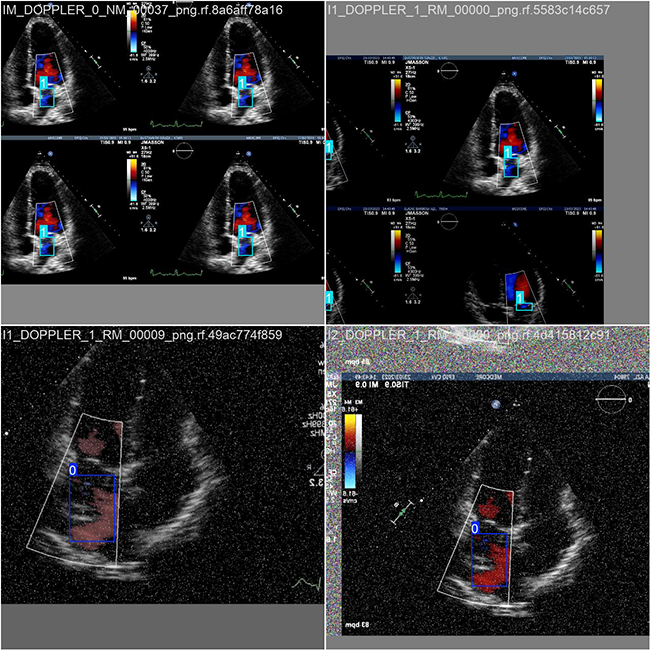

2.数据集准备与训练

本研究使用了包含心脏右心室医学影像分析的数据集,并通过 Labelimg 标注工具对每张图像中的目标边界框(Bounding Box)及其类别进行标注。基于此数据集,采用 YOLOv8n 模型进行训练。训练完成后,对模型在验证集上的表现进行了全面的性能评估与对比分析。整个模型训练与评估流程包括以下步骤:数据集准备、模型训练、模型评估。本次标注的目标类别主要集中于心脏右心室医学影像分析。数据集总计包含 1834 张图像,具体分布如下:

训练集:1283 张图像,用于模型学习和优化。

验证集:367 张图像,用于评估模型在未见过数据上的表现,防止过拟合。

测试集:184 张图像,用于最终评估模型的泛化能力。

部分数据集图像如下图所示:

部分标注如下图所示:

这种数据分布方式保证了数据在模型训练、验证和测试阶段的均衡性,为 YOLOv8n 模型的开发与性能评估奠定了坚实基础。